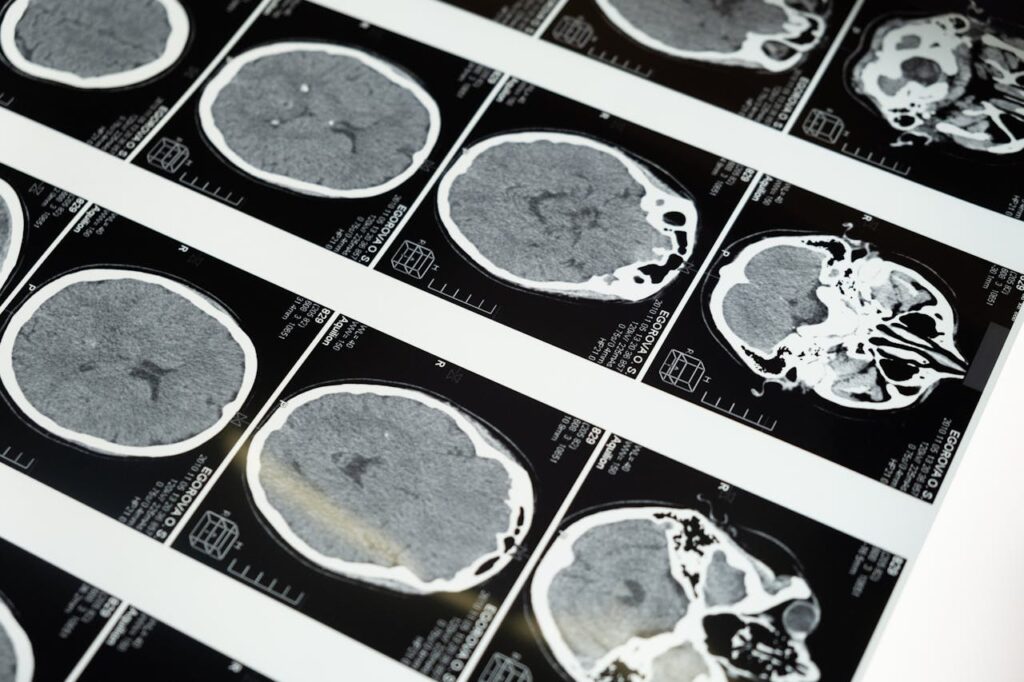

El estudio también señala alteraciones en el control inhibitorio, habilidad fundamental para regular conductas y evitar impulsos. Investigaciones electrofisiológicas muestran que quienes consumen videos cortos de manera excesiva exhiben menor actividad cerebral en tareas de atención. Dicho de otra forma, los cerebros más expuestos al flujo constante de estímulos adquieren menos capacidad para filtrar información irrelevante y priorizar lo importante.